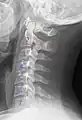

X-ray of cervical vertebrae